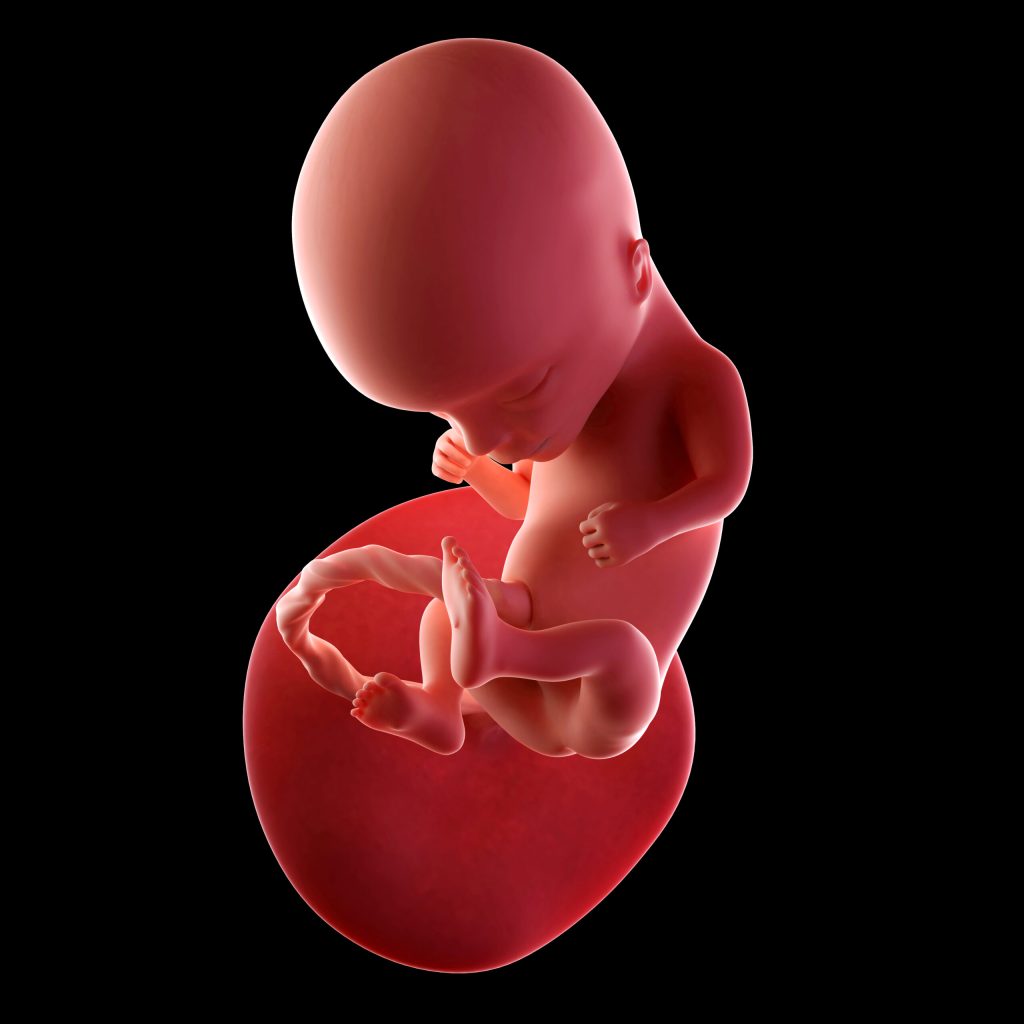

Week 13

Rond deze tijd, aan het begin van de 4e maand, wordt de huid van je baby bedekt met een laagje donshaartjes. Deze zachte haartjes worden lanugo genoemd en verdwijnen weer vrijwel volledig tegen de uitgerekende datum. De huid is doorzichtig en alle adertjes zijn zichtbaar. De spieren in het gezicht ontwikkelen steeds verder en je baby kan nu allerlei gezichtsuitdrukkingen aannemen. Ook beginnen de reflexen zich te ontwikkelen. Kleine jongetjes beginnen al testosteron aan te maken.

8 cm

30 g